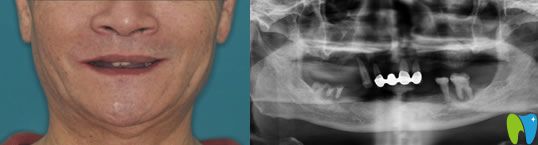

【全口種植牙前后對(duì)比圖】

種植牙前:全口牙缺失;

種植牙后顧客評(píng)價(jià):自己在智媄口腔做的全口種植牙吃東西和真牙一樣,已經(jīng)幾年了,但是醫(yī)護(hù)人員每年都會(huì)提醒過(guò)來(lái)復(fù)查,服務(wù)和技術(shù)都很好!

佛山智媄口腔全口種植牙案例